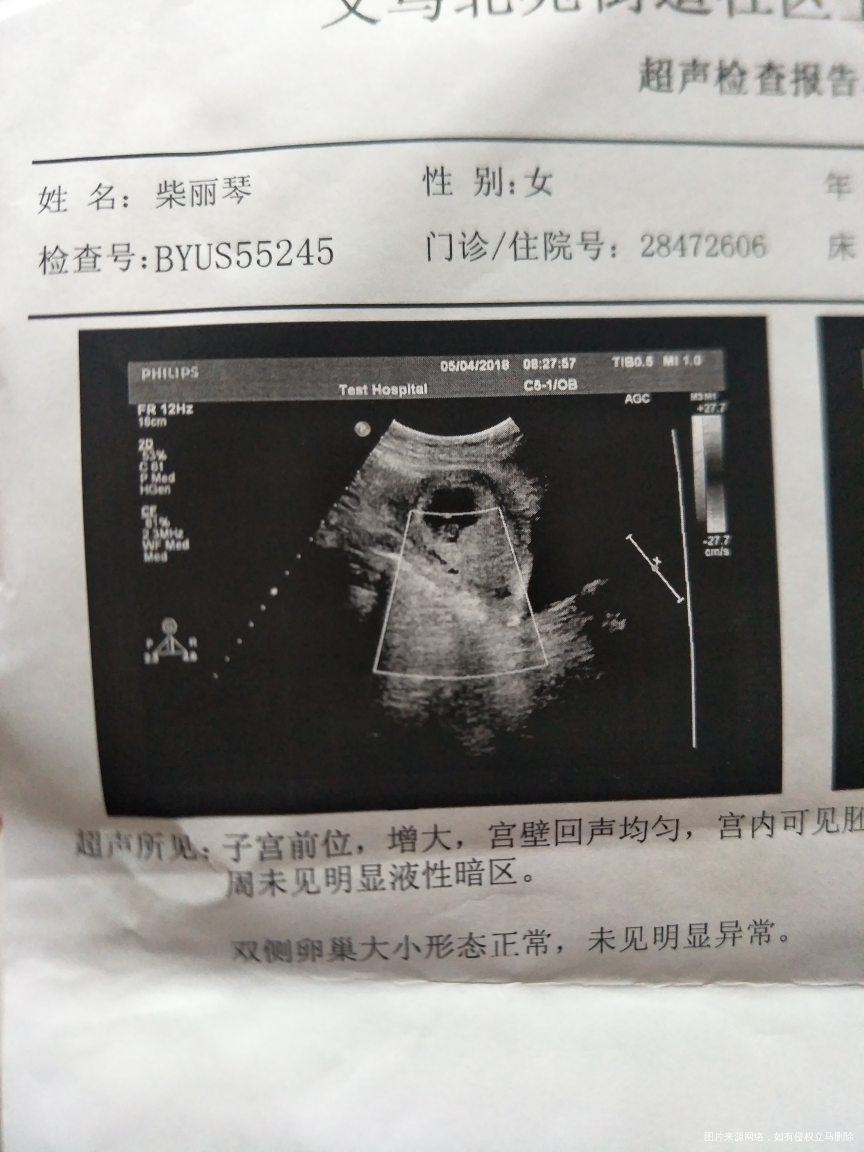

能看的出男孩女孩吗?这是第一

次b超

看妊娠囊没有任何依据的

看孕囊有点像女孩哦

单子看不出来的,孕囊也看不出来,B超还有失误的时候,18周看彩超应该看出来

要长条形才是男孩,你这个有点圆形,估计女孩子的机率大一些